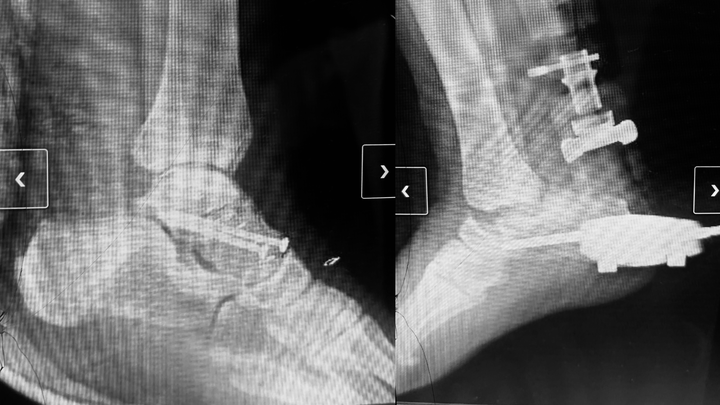

His left foot is broken and now held together with screws. His right foot suffered catastrophic damage; his talus bone popped out of his ankle, and his foot was nearly severed, held on only by tendons and skin. At the scene, I applied two tourniquets and elevated his leg to stop the bleeding by his instruction that he was able to give calmly despite the pain until paramedics arrived. When they eventually arrived, one of the paramedics foolishly stepped on his left foot, causing him immense pain. Even after yelling at him over and over, he just kept stepping on him.